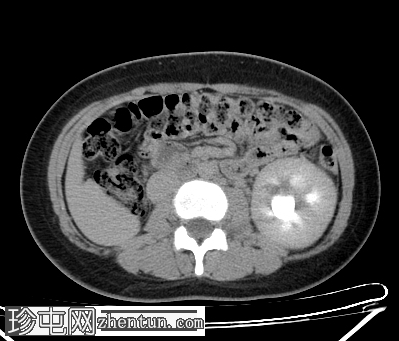

CT扫描

轴向扫描

非造影

轴向扫描C+期

动脉期

门静脉期

延迟扫描

腹部CT平扫和造影扫描显示左肾实质增大,伴I级肾积水,右肾在肾窝内未见异常。双子宫完整(两个子宫体和两个宫颈),阴道隔膜将阴道分成两半,阴道右半部分积液,非造影片上积液密度较大,提示为

血液

(阴道积血)。

增强扫描图像提示存在一条血管分支压迫左肾盂-输尿管连接处,导致肾积水。

道格拉斯囊内有少量游离液体。

右侧卵巢可见黄体。

其他腹部器官未见异常。

CT和MRI检查结果为Herlyn-Werner-Wunderlich综合征的典型表现,其特征为经典的三联征:III型苗勒氏管异常(完全性双子宫)、中肾管异常(肾发育不全)以及肾发育不全侧阴道积血。

该患者左肾积水是偶然发现的,且无任何明确的梗阻原因,例如泌尿系统结石、

肿瘤

或炎症。积水延伸至左肾盂-输尿管连接处,疑似存在血管分支交叉,该分支可能造成压迫,从而导致肾积水。